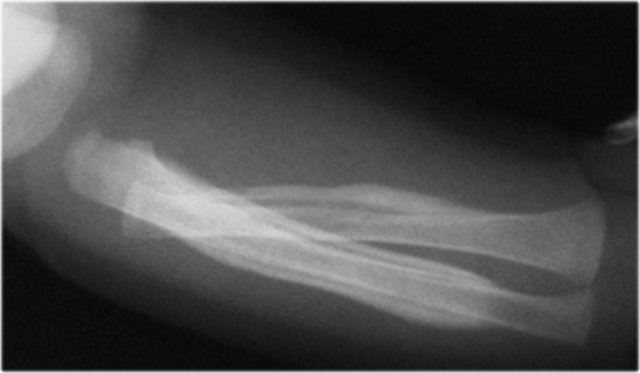

Images

Bucket handle fracture in proximal tibia. The metaphyseal fracture fragment is seen as a disk or bucket handle.